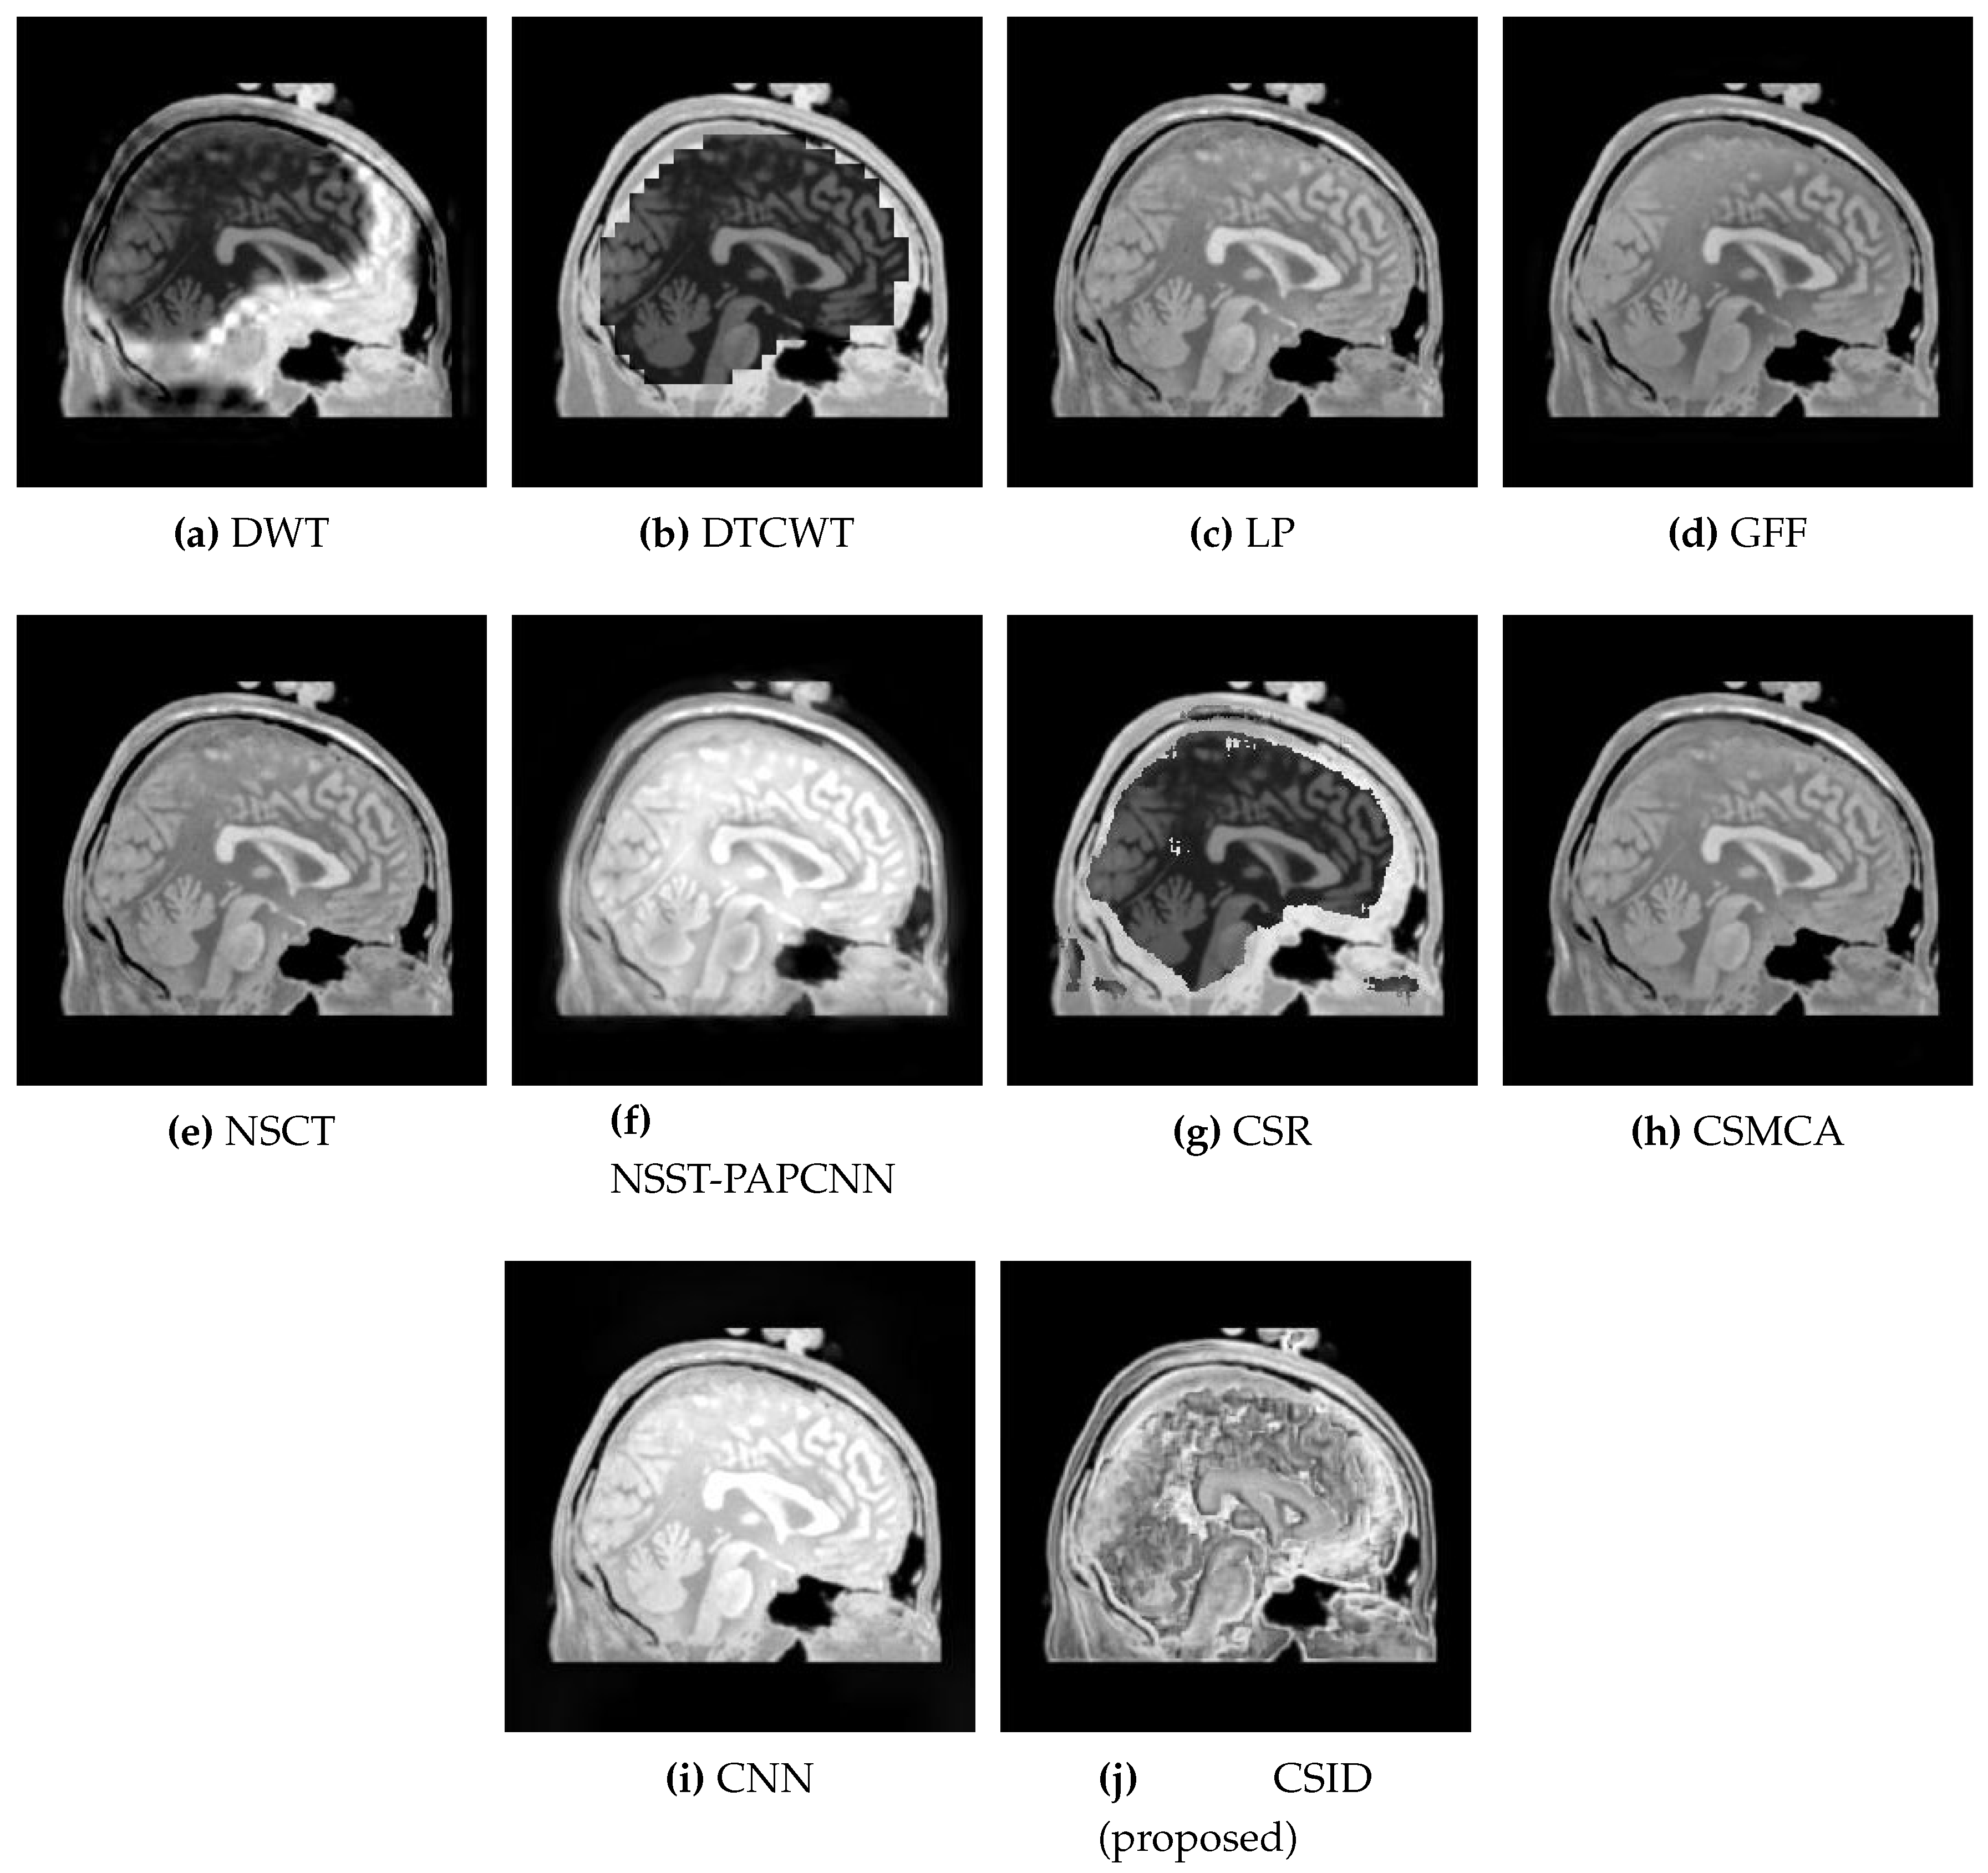

Similarly, Figure 6 shows the qualitative visual analysis for the Data-2 dataset. As a result of the smaller MI score, DWT (Figure 6a), NSCT (Figure 6e), and CSR (Figure 6g) show the highest information loss, among the selected algorithms, for the overlapping areas in MRI and CT images that result in visual deformations of the fused images. Similarly, CNN (Figure 6i) also does not remain effective in transferring information from the source images. The following section (Section 5.2.2) provides quantitative analysis with respect to the given objective evaluation metrics (as discussed in Section 4) that affirms the aforementioned statements. Moreover, in addition to MI, F M I m x , y and Q A B / F evaluation metrics also remain critical that relates to accuracy in the resultant fused images. Although, GFF, NSST-PAPCNN, and CSMCA provide better results in comparison with DWT, NSCT and CSR by conveying complementary information into the fused image, but these algorithms lack accuracy (as shall be discussed in Section 5.2.2 through quantitative analysis). In the end, note that our proposed algorithm (Figure 6j) provides better visual effects in comparison with the other aforementioned algorithms, due to its improved information extraction and edge detection abilities.

Figure 6. Comparative analysis, based upon visual observation, of the resultant fused images generated by the given set of algorithms using Data-2 dataset.

Diagnostics 10 00904 g006